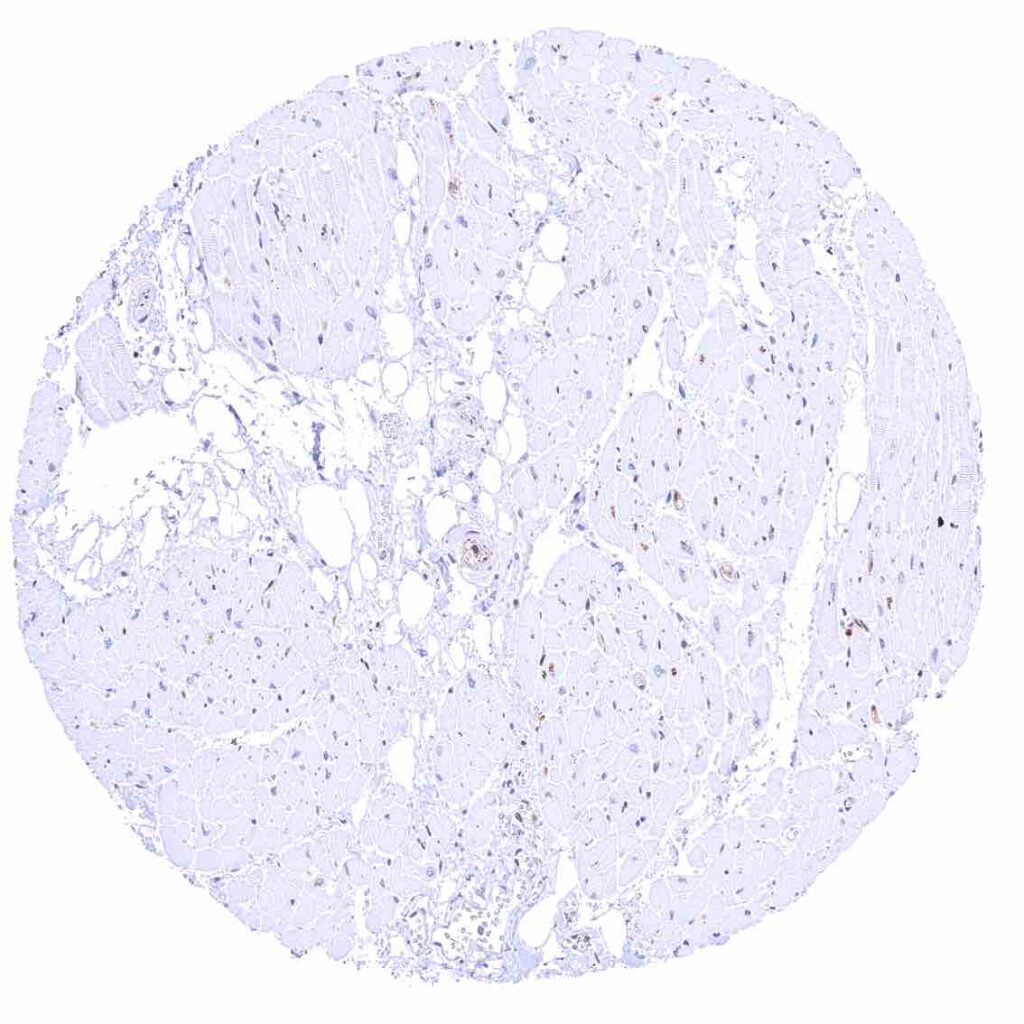

Fat – Variable nuclear p27 staining of at least a fraction of fat cells.